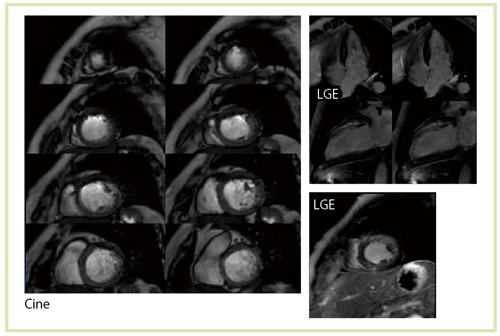

心臓MRIにおける3T装置では,1.5T装置で主流となっていたTrueSSFP法が利用しづらい。これは静磁場とRF磁場の不均一や,SARの制約を受けるためである。3T装置によるシネMRIでは,susceptibility artifactやbanding artifactが目立つようになる(図9)。この問題については,中心周波数(f0)をシフトさせることで,アーチファクトを抑えるといった回避策が考え出された。中心周波数(f0)を0ppm,1.0ppm,1.5ppmと変化させると,図10のようにbanding artifactが画面上方にシフトすることがわかる。心臓の場合,関心領域が狭いので,心臓以外にbanding artifactをずらすことで,良好な画像を得ることができる(図11)。

図11 SSFP法によるシネMRI(Titan 3T) 陳旧性心筋梗塞 TR/TE=3.4/1.7,FA42

図11 SSFP法によるシネMRI(Titan 3T)

陳旧性心筋梗塞

TR/TE=3.4/1.7,FA42

3Tの高SNRを thin sliceに生かす

さらに,心臓MRIにおける3T装置の特徴として最も強調すべきは,SNRの高さをthin sliceに生かすことができることである。1.5T装置では,thin slice画像は実用的ではなかったが,3T MRIでは積極的に使えるようになった(図13,14)。thin slice 撮像のメリットを,われわれは心臓の遅延造影法として,whole heart late gadorinium enhancement法に用いることとした。マルチスライスCTの撮影のように,心臓を薄いスライス厚で撮像し,それを再構成することで,短軸像,長軸像,四腔断像など,いろいろな方向からの観察が可能になる。1.5T装置の場合,スライス厚が3mm,スライス間補間が1.5mmであったが,3T MRIではそれぞれ1.5mm,0.75mmとなり,高い空間分解能を持った再構成画像を得ることができる(図15)。